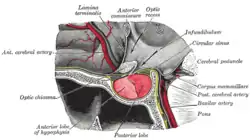

The pituitary gland or hypophysis is often referred to as the "master gland" of the human body. Part of the hypothalamic-pituitary axis, it controls most of the body's endocrine functions via the secretion of various hormones into the circulatory system. The pituitary gland is located below the brain in a depression (fossa) of the sphenoid bone known as the sella turcica. Although anatomically and functionally connected to the brain, the pituitary gland[43] sits outside the blood–brain barrier. It is separated from the subarachnoid space by the diaphragma sella, therefore the arachnoid mater and thus cerebral spinal fluid cannot enter the sella turcica.

The pituitary gland is divided into two lobes, the anterior lobe (which accounts for two thirds of the volume of the gland), and the posterior lobe (one third of the volume) separated by the pars intermedia.[7]

The posterior lobe (the neural lobe or neurohypophysis) of the pituitary gland is not, despite its name, a true gland. The posterior lobe contains axons of neurons that extend from the hypothalamus to which it is connected via the pituitary stalk. The hormones vasopressin and oxytocin, produced by the neurons of the supraoptic and paraventricular nuclei of the hypothalamus, are stored in the posterior lobe and released from axon endings (dendrites) within the lobe.[44]

The pituitary gland's anterior lobe (adenohypophysis) is a true gland which produces and secretes six different hormones: thyroid-stimulating hormone (TSH), adrenocorticotropic hormone (ACTH), follicle-stimulating hormone (FSH), luteinizing hormone (LH), growth hormone (GH), and prolactin (PRL).[45]